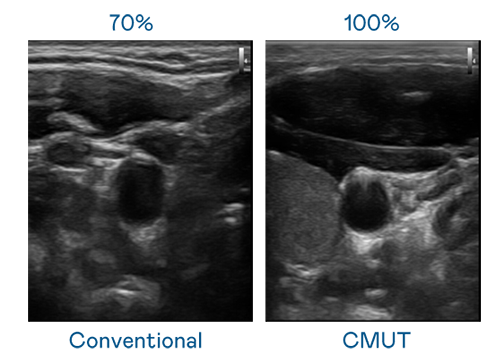

CMUT 技术是一种用电容式微机电元件来产生超音波讯号的技术。与传统 PZT 压电式技术相比,CMUT 频宽增加 30%,更宽频的超音波讯号让影像解析度大幅提升,是实现高影像品质医疗超音波扫描、促进精准医疗发展的关键技术。

超音波影像的解析度高低,首先取决于探头能发出的讯号频宽。k8凯发 CMUT 可提供高清晰的超音波讯号,提供高频宽、高灵敏度、影像纹理细节更高的超音波影像,协助医护人员缩短影像判读时间及利用精准的医疗影像进行诊断。